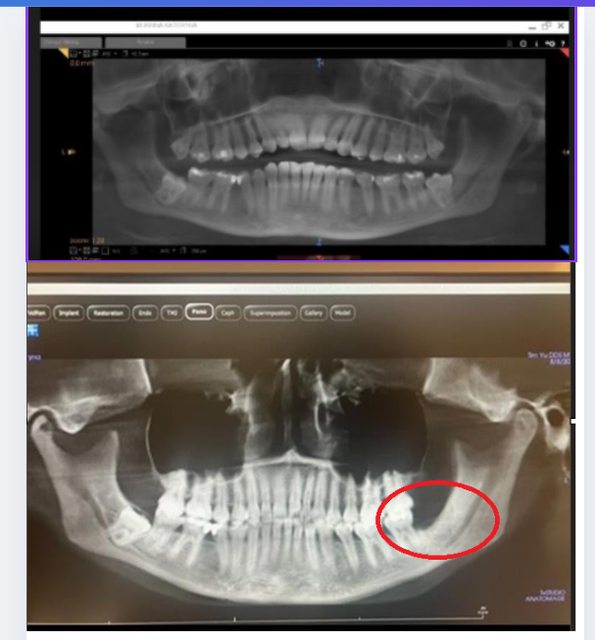

photo 1 (December 2023) before removing 4 wisdom teeth (4 teeth are crooked as in the photo)

photo 2 (July 2024), after removing 4 wisdom teeth almost 1 year

recently no x-ray or 3d CT, as you can see, photo number 2, the two corners of the bone base in the area of the 8th tooth of the lower jaw and upper jaw are very full again, about 70% 80% compared to the original . In this picture of me with my mouth open, you can see the bones and gums protruding instead of the bone loss.